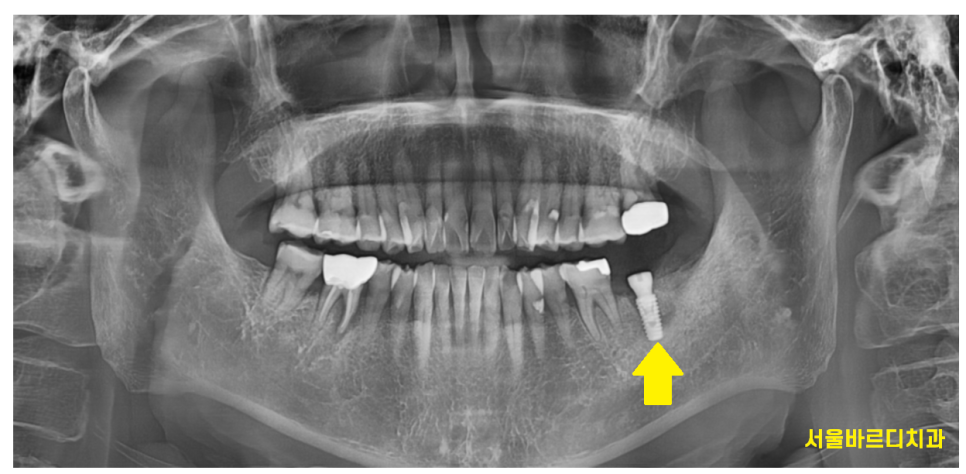

아픈 왼쪽 아래 부위는

발치한 당일에 하남 미사 치과에서

임플란트를 심어 드렸습니다.

230926

치료 기간을 단축하기 위해서라면

중간에 수술을 하였어도 되었지만습니다.

임플란트 치료 경험이 없으셨기에

한쪽 우선 끝내놓고

임플란트 치료의 전 과정을 겪어보게 한 후

반대편 수술을 진행하였습니다.

240329